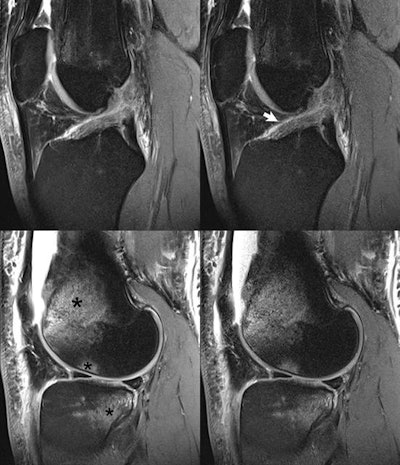

The use of simultaneous multislice imaging for abbreviated scan times in a trauma patient (motorcycle accident). A ruptured anterior cruciate ligament (arrow) is seen on (top row) sagittal proton density-weighted images acquired at 3-tesla, together with (bottom row) bone marrow edema (asterisk) of the distal femur, lateral femoral condyle, and posterolateral tibial plateau. Depiction is essentially equivalent on the scans without and with simultaneous multislice imaging. The simultaneous multislice imaging scan, due to use of two times acceleration, required only 1:34 min:s for acquisition, approximately half that for the nonsimultaneous multislice imaging scan. All images courtesy of Investigative Radiology (January 2017, vol. 52:1, pp. 1-17).The use of simultaneous multislice imaging for abbreviated scan times in a trauma patient (motorcycle accident). A ruptured anterior cruciate ligament (arrow) is seen on (top row) sagittal proton density-weighted images acquired at 3-tesla, together with (bottom row) bone marrow edema (asterisk) of the distal femur, lateral femoral condyle, and posterolateral tibial plateau. Depiction is essentially equivalent on the scans without and with simultaneous multislice imaging. The simultaneous multislice imaging scan, due to use of two times acceleration, required only 1:34 min:s for acquisition, approximately half that for the nonsimultaneous multislice imaging scan. All images courtesy of Investigative Radiology (January 2017, vol. 52:1, pp. 1-17).